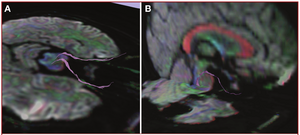

Publication: PLoS One. 2015 Oct 7;10(10):e0139434. PMID: 26444010 | PDF Authors: Tax CM, Chamberland M, van Stralen M, Viergever MA, Whittingstall K, Fortin D, Descoteaux M, Leemans A. Institution: Image Sciences Institute, University Medical Center Utrecht, Utrecht, The Netherlands. Background/Purpose: Fiber tractography plays an important role in exploring the architectural organization of fiber trajectories, both in fundamental neuroscience and in clinical applications. With the advent of diffusion MRI (dMRI) approaches that can also model "crossing fibers", the complexity of the fiber network as reconstructed with tractography has increased tremendously. Many pathways interdigitate and overlap, which hampers an unequivocal 3D visualization of the network and impedes an efficient study of its organization. We propose a novel fiber tractography visualization approach that interactively and selectively adapts the transparency rendering of fiber trajectories as a function of their orientation to enhance the visibility of the spatial context. More specifically, pathways that are oriented (locally or globally) along a user-specified opacity axis can be made more transparent or opaque. This substantially improves the 3D visualization of the fiber network and the exploration of tissue configurations that would otherwise be largely covered by other pathways. We present examples of fiber bundle extraction and neurosurgical planning cases where the added benefit of our new visualization scheme is demonstrated over conventional fiber visualization approaches. Funding:

|